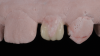

(2.) Pretreatment smile, left lateral smile, and right lateral smile photographs, respectively, showing the patient’s peg-shaped lateral incisors.

Figure 2

(3.) Pretreatment smile, left lateral smile, and right lateral smile photographs, respectively, showing the patient’s peg-shaped lateral incisors.

Figure 3